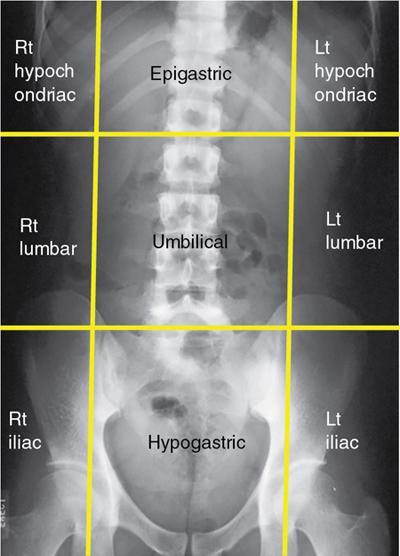

UNDERSTANDING THE ADULT ABDOMINAL RADIOGRAPH: TECHNIQUES AND INTERPRETATION Tanvi Modi Radiography of the abdomen is a common practice for the evaluation of abdominal organs. The anatomy and pathology of digestive, hepatobiliary and genitourinary systems can be assessed using radiographs, either as a stand-alone practice or as a primary imaging modality followed by contrast studies, ultrasound or cross-sectional imaging. In addition, abnormalities of the musculoskeletal or integumentary system can also be deduced on the basis of abdominal radiographs. This chapter intends to give an overview on the techniques and positioning in abdominal radiography as well as interpretation of normal and abnormal features. While superior imaging modalities such as ultrasound, computed tomography (CT), magnetic resonance imaging, capsule endoscopy and the likes have taken over abdominal imaging by and large, radiography still holds a pivotal role in certain situations and conditions, such as: The standard abdominal radiograph is taken in supine position and anteroposterior projection. This is also popularly known as the KUB (kidneys-ureters-bladder) radiograph. Previously, supine as well as erect radiographs were performed in all patients; however, this is not commonly done due to high-radiation dose. For all indications of abdominal radiography, including acute abdomen, supine radiographs are sufficient in terms of radiographic diagnosis, with the exception of perforation for which an erect chest or lateral decubitus radiograph can be performed if there is clinical suspicion. Patient should lie supine on the imaging table with median sagittal plane at right angles to the table and coincident with the midline of the table (Fig. 7.1.1.1). The body is divided into equal right and left halves by the median sagittal which passes through the sagittal suture of the skull. Pelvis should be adjusted so that the anterior superior iliac spines are equidistant from the table top. Gonadal shields, in the case of male patients, should be placed with the upper edge of the shield at the level of pubic symphysis. Although rarely used for female patients, these should be positioned between the anterior superior iliac spines and the pubic symphysis. The centre point of the image receptor should be approximately located at a point 1 cm below the line joining the iliac crests. The X-ray beam should be in a vertical direction, perpendicular to the table top and image receptor at the centre point. Collimation should be such that the soft tissue and subcutaneous region along lateral aspects of the abdominal cavity should be covered within the image. Also, the superior extent involving diaphragm and inferior extent involving the inferior pubic rami is important to look for any lower chest pathologies or any inguinal hernia. 35 × 43 cm (14 × 17 inches) in portrait orientation. On an average, abdominal radiograph exposes a patient to a dose of approximately 1.5 mSv, which is equivalent to 75 chest radiographs or 1/6th dose of a standard CT of the abdomen. The entrance skin dose is approximated to be 4 mGy. At such an effective dose, the additional lifetime risk of fatal cancer is 1 in 30,000. The exposure time is kept short. Patient is asked to exhale completely and hold their breath, with exposure taken at this point of full expiration to ensure imaging of abdominal organs in their natural positions. Modifications of this technique can be made depending on patient habitus and clinical condition. Kilovoltage peak (kVp) should be set to allow adequate visualization of abdominal soft tissue structures as well as semiopaque renal and biliary calculi. Average kVp is set at 70–85 kV. 102 cm (40 inches) Grids are commonly used to reduce scatter radiation. Placement of side marker on the image receptor at the time of radiographic exposure is essential. Bowel pattern depiction should be such that there is minimal lack of sharpness. Standard guidelines for abdominal radiography dictate that the radiograph should extend from the diaphragm up to the level of inferior pubic rami and must include the lateral abdominal wall musculature. The abdomen is divided into four quadrants on the basis of two perpendicular lines (Fig. 7.1.1.7). The vertical line passes through the mid sagittal plane and crosses the umbilicus and symphysis pubis. The horizontal line is a transverse line across the umbilicus at 90 degrees to the vertical line and is situated at the level of L4–L5 intervertebral disc. The quadrants are as follows: Another division system is dividing the abdominopelvic cavity into nine regions using two vertical and two horizontal planes (Fig. 7.1.1.8). The vertical planes, also known as the right and left lateral planes, are parallel to the midsagittal plane between midline and anterosuperior iliac spines on either side. Of the two horizontal planes, the upper transpyloric plane is at the level of lower border of L1 and the lower transtubercular plane is at the level of L5. The nine regions are: On a standard radiograph, the exposure should be such that the stomach, bowel loops, outlines of liver, spleen, kidneys, psoas muscles should be well identified. Also, lumbar transverse processes should be seen. Arch of the pubic symphysis should be visible to evaluate bladder region. A well-centred film without rotation will demonstrate bilaterally symmetrical lower ribs, iliac wings, ischial spines and obturator foramina. Different structures seen on an abdominal radiograph can be classified into five basic densities: Identification of different structures depends on the relative degree of contrast between their densities. The demarcation is clearer in chest and is diminished in abdomen due to relative similar soft tissue density of various structures. On a normal radiograph, relatively large amounts of gas in stomach and colon with minimal small bowel gas can be seen. Further, colonic gas can vary from negligible to extensive, mimicking obstruction pattern; however, usually the gas is enough to delineate colonic haustral pattern. Faecal matter gives a mottled appearance to colonic gas. Short-air fluid levels on an erect radiograph may be seen even in normal cases. The normal appearance of small bowel loops on an abdominal radiograph follows the rule of threes: Stomach is seen in the left upper quadrant and is visualized when distended with air. It is commonly seen extending from T11 to L2 level. Common feature identifying the stomach is the fundal gas which is usually seen as an air fluid level within the gastric lumen. Small bowel loops are distributed to the centre of the abdominal cavity and large bowel loops are peripheral. Duodenum is predominantly situated in right upper quadrant. It extends to left upper quadrant in the region of duodenojejunal flexure. Jejunum occupies the left upper and lower quadrants and is easily identified due to the presence of thick, numerous, closely spaced valvulae conniventes (Fig. 7.1.1.9A). The ileum occupies both lower quadrants and extends into right upper quadrant. Ileum has few and less prominent valvulae as compared to jejunum (Fig. 7.1.1.9B). Ascending and descending colon are retroperitoneal and have relatively fixed positions along lateral aspect of the abdominal cavity on either side. Transverse and sigmoid colon, on the other hand, may have a variable position due to their mobility along mesocolon and redundant pattern. These can be identified with confidence on account of haustrations and faecal matter (Fig. 7.1.1.10). Haustrations are usually well seen in ascending and transverse colon and poorly delineated beyond splenic flexure. Caecum is in the right lower quadrant, though it may be mobile or pulled up. Rectal gas is usually seen in the midline at the level of pelvis and its presence rules out large bowel obstruction. All these positions may vary due to anatomical conditions such as malrotation or pathological conditions, for example volvulus. Liver, spleen and renal outlines cannot be completely traced with precision due to the overlap by bowel loops. On a frontal projection, the liver appears as a triangular structure occupying right and left hypochondrium and epigastric region. Occasionally, the right lobe may be seen extending lower than the right renal shadow. This is a normal variant known as Reidel’s lobe. Gall bladder is situated in the posterior and inferior region of the liver and any pathology of the gall bladder should be looked for in this region. On a lateral radiograph, the gall bladder is anterior to the midcoronal plane. This helps in distinguishing gall bladder calculi from renal calculi, which will be more posteriorly situated. Spleen is seen in left upper quadrant/left hypochondrium, flushed to left lower ribs and left hemidiaphragm. Pancreas is present in the epigastric region (right and left upper quadrants) and is usually not identified in the absence of a pathology. The kidneys are bean-shaped retroperitoneal organs which are seen on either side of the vertebral column and lateral to psoas muscles. Due to the presence of liver on the right side, this kidney is slightly lower in position as compared to its contralateral counterpart. The visualization of kidneys on radiographs is facilitated by the surrounding fatty capsule. Kidneys lie between T11–12 and L2 level, with left kidney 1 cm higher than the right. Psoas muscle shadow can be normally seen along lateral aspect of lumbar spine bilaterally and is mildly concave (Fig. 7.1.1.11). Abdominal wall muscles are not routinely assessed on radiography; however, inclusion of lateral abdominal wall (muscles as well as subcutaneous plane) is a must while performing radiography. The flank stripe or the properitoneal fat stripe is a fat density linear concavity seen along lateral abdominal wall (Fig. 7.1.1.11). It is bound by the paracolic gutters and air-filled ascending and descending colon. All the solid organs in the abdomen are identified due to the fat density outlining them. Distortion of these fat lines helps in identifying organomegaly or focal mass lesions. The dome of urinary bladder is outlined by fat, which aids in differentiating its density from other soft tissue structures of the pelvis. Not all calcifications seen on abdominal radiograph are abnormal. Some may depict age-related changes such as vascular calcifications involving abdominal aorta, pelvic vessels, splenic artery in the region of left upper quadrant. Within the pelvis, phleboliths may be seen and mistaken for urinary calculi. Assessment of lumbosacral spine, iliac bones and femoral heads can be made on the basis of plain radiography. Degenerative changes may be commonly seen. Lower ribs can also be evaluated for pathologies. Dilated small bowel loops with rounded soft tissue density in midline over umbilical region suggests obstruction secondary to umbilical hernia. Pneumoperitoneum must be looked for in all cases of acute abdomen. While erect chest and left lateral decubitus radiographs can detect even 1 mL of free air, there are multiple signs on supine radiograph to suggest this diagnosis, for example Rigler’s sign, falciform ligament sign, football sign (Figs. 7.1.1.24 and 7.1.1.25). Retroperitoneal perforation may demonstrate air outlining psoas muscles and retroperitoneal organs. Small amount of free air may persist in the abdominal cavity up to 3 weeks after surgery, although it usually resolves within a week. Clinical history is important in such cases. Air foci within the bowel wall may represent bowel ischaemia/strangulation. Linear gas patterns in right hypochondrium may be due to two causes, that is pneumobilia and pneumoporta. The former can be seen normally postbiliary surgery, sphincterotomy, ERCP or in the case of abnormal fistulous communication between bowel and biliary tree (Fig. 7.1.1.26A). Pneumoporta (Fig. 7.1.1.26B) is a red flag and warrants further investigation to look for conditions such as mesenteric ischaemia and toxic megacolon. Pneumobilia is more centrally located whereas air shadows in pneumoporta are seen reaching up to periphery of liver. Air foci over renal shadows (Fig. 7.1.1.27), gall bladder or pancreas, in the absence of recent procedural history, suggest fulminant infection and mandate urgent intervention. Central midline calcific foci between T9 and T12 vertebrae can be attributed to calcific pancreatitis (Fig. 7.1.1.28). In the left upper quadrant, areas of calcification seen involving a shrunken spleen may be seen in autosplenectomy. In right upper quadrant, calcified gall stones may be seen. These tend to be small, multiple, uniformly circumscribed and ring-like in appearance with central translucency (Fig. 7.1.1.29A). Mercedes Benz sign, a triradiate pattern of gas lucency, is associated with gallstones. In contrast, renal calculi are more commonly solitary, irregular, of homogenous density, conform to renal calyceal or pelvic outline (Fig. 7.1.1.29B) and are sometimes of staghorn configuration. On lateral view, the gall stones are more anteriorly located as compared to renal calculi, which may be partly superimposed on lumbar vertebrae. Ureteric calculi tend to overlap bony structures such as lumbar transverse processes (Fig. 7.1.1.29B) or sacroiliac joints. Extensive or patchy, curvilinear calcification of gall bladder wall is known as porcelain gall bladder which is often associated with malignant transformation. Calcification involving adrenal glands may be secondary to infection or haematoma, or a congenital condition known as Wolman’s disease where there is bilateral involvement. Discontinuous discrete midline tram track calcification in the abdomen may indicate atherosclerotic changes in abdominal aorta and branch vessels. However, when the calcification is in a globular pattern and seen below the level of L2 vertebra, aortic aneurysm should be suspected (Fig. 7.1.1.30). Appendicoliths, though not commonly seen, may sometimes be detected in right iliac region. Pelvic calcifications: vesical calculi, distal ureteric or vesicoureteric junction calculi, calcified fibroids, ovarian dermoid with tooth-like calcifications (Fig. 7.1.1.31) may be the cause of abdominal pain and should be diligently looked for. Vesical calculi are usually more large and central in location whereas calcification due to fibroids may be more lateral. Schistosomiasis is another cause of bladder wall calcification, as is calcification of bladder tumours. Phleboliths tend to be bilaterally symmetrical, with a lucent centre unlike ureteric calculi. While it is believed that phleboliths are located below the level of ischial spines and ureteric calculi above, this is not always true and should be confirmed with CT. Fluid may collect adjacent to properitoneal fat line, forming a linear soft tissue density separating the fat line from the ascending or descending colon. Hellmer’s sign demonstrates medial displacement of lateral edge of liver (hepatic angle), due to fluid collection or ascites. Gross ascites may appear as generalized abdominal haziness or diffuse increased density of pelvis. Abscesses can involve any solid organ and in such cases may be difficult to demonstrate on plain radiography alone. Enlargement of organ or faint gas densities within can be suggestive of the same. In the case of peritoneal abscess, mottled density due to air, fluid and necrotic contents point towards this diagnosis, especially in right iliac fossa in association with appendicitis. Retroperitoneal abscess, similar to any retroperitoneal mass, may cause displacement of retroperitoneal structures (Fig. 7.1.1.32). Subdiaphragmatic abscesses may show concomitant ipsilateral pleural effusion (Fig. 7.1.1.33). These should be differentiated from Chilaiditi syndrome. Fluid and soft tissue lesions present with the same density on radiographs. While it is difficult to characterize the lesion and organ of origin, clues for the same can be provided by organomegaly (Fig. 7.1.1.34), distortion of fat surrounding solid organs, displacement of bowel loops or solid organs. For example, a retroperitoneal lesion may cause anterior or inferior displacement of kidney, a pelvic mass may cause upward displacement of small bowel loops. Different densities such as fat or calcification may help in identifying organ of origin (e.g. fat and tooth densities seen in ovarian dermoid). Convexity of margins of psoas muscle on an abdominal radiograph can be due to haematoma, abscess or intramuscular tumour. Radiographs are performed for the initial diagnosis of foreign body in the abdomen including type, number of foreign bodies, location, size and shape (Fig. 7.1.1.35). Radiolucent foreign bodies such as wood, plastic, chicken bones will not be easily identified on radiography. Low kVp (65–70 kVp) can increase contrast and help identify these objects. In addition to an abdominal radiograph, chest radiography is also performed to exclude aspiration or oesophageal location of foreign body. Ingested or introduced foreign bodies may cause complications such as obstruction, perforation, fistula formation and sepsis. Hence, once their presence is confirmed, follow up radiography must be performed until they are eliminated. One must look for fractures/dislocation injuries involving the vertebrae or pelvic bones, especially after history of trauma. Lucent expansile lesions or sclerotic bony deposits which represent neoplasms, absent pedicle sign in cases of metastasis, metabolic bony changes such as rugger jersey appearance, Paget’s disease, arthropathies such as ankylosing spondylitis with bamboo spine appearance and sacroiliitis (Fig. 7.1.1.36) are some of the conditions which may be diagnosed based on an abdominal radiograph. Overlap of bowel loops over iliac blades may lead to a misdiagnosis of lucent lesions and should be evaluated with caution. Basal pneumonia may be the cause of acute abdominal pain and should be looked for in abdominal radiography. Similarly, pleural effusion, pericardial effusion, calcified pleural plaques, achalasia, interstitial fibrosis are few other findings that can be seen in lower chest on an abdominal radiograph. Basilar atelectasis can give a deceptive appearance of pneumoperitoneum (Fig. 7.1.1.37). Surgical clips, commonly in right hypochondrium after cholecystectomy, drainage tubes, ventriculoperitoneal shunts, femoral line catheters, IVC filters, stents (vascular, renal, biliary) (Fig. 7.1.1.38), stoma bags, contraceptive devices are some structures that may be seen in an abdominal radiograph. Correct knowledge of patient history and normal locations of these structures prevents misdiagnosis. Certain artefacts may be projected upon the radiograph due to surface structures such as trouser buttons, body piercing, sequins over clothing and should not be considered as a pathology. Multiple skin surface nodules in cases of neurofibromatosis, soft tissue focal swellings, such as abscesses, lipomas, haematomas, desmoid tumours and malignant lesions may be incidentally seen on radiography. These can be further evaluated using ultrasound or CT. Subcutaneous emphysema is another finding that may be seen in lower abdominal wall secondary to retroperitoneal perforation or diffusely along abdominal wall in the case of bowel perforation (Fig. 7.1.1.39). Foreign bodies such as bullets and pins may be seen lodged in abdominal wall. A systematic approach to abdominal radiographs is important for accurate diagnosis as follows: Despite the development of newer techniques for imaging of the abdomen, plain radiography still holds an important place in the initial assessment of acute abdomen. Positive and negative findings on an abdominal radiograph can direct further investigation. Ideal positioning, recognition of normal appearances and keen scrutiny for pathologies is a sine qua non for radiologists reading a plain film of the abdomen. OESOPHAGOGRAM Padma V. Badhe, Vikram Reddy, Sultan Moinuddin Shaukatali, Zillani Alam, Ravi Varma, Abhishek Bairy, Dasari Ravikiran, Revati Tekwani, Soniya Patankar, Megha Nair, Gautham Shankar Oesophagogram is the process of obtaining radiological images and simultaneous motion recording to evaluate function and disorders of pharynx, oesophagus and proximal stomach. Oesophagogram is usually done primarily to evaluate dysphagia. Some of the common indications are oesophageal motility disorders, strictures, gastro-oesophageal reflux disease (GERD) and suspected masses. It can also be used to detect uncommon anomalies like vascular rings/slings and aberrant anatomy. It also helps to evaluate further in cases where there is inability to pass upper GI scope. Double-contrast oesophagogram is mainly indicated in early mucosal disease like erosion, polyp, infection and tumours. If a motility disorder is suspected, dynamic technique (e.g. videofluoroscopy) is used for dysphagia or aspirations in cases of stroke, neuromuscular disorders, post head and neck surgery or radiation. Barium oesophagogram is contraindicated in suspected cases of perforation and tracheoesophageal fistula, aspiration, rarely if there is hypersensitivity to barium suspensions. It is also contraindicated in suspected oesophageal perforation where a water-soluble contrast agent is more suitable. However, ionic water-soluble contrast agent is better avoided in cases of aspiration or fistula with airway. The contrast examination of the pharynx is dangerous in cases of acute epiglottitis and must be ruled out on plain radiograph. An 80% w/v barium suspension is used in full column views. However, 200%–250% w/v barium suspensions is usually required for mucosal relief films. The barium sulphate mixture is fed to the patient either by spoon, by glass, or through a drinking straw, depending on its consistency. In videofluoroscopy, the pharyngeal phase of swallowing is usually safer with barium pudding than with thick barium and safer with thick barium than with thin barium. However, if the major abnormality is poor pharyngeal contraction leading to stasis in the piriform sinus (and epiglottic tilt is normal), a thin liquid is safer. Epiglottic motility is better assessed with thin barium because thick barium often obscures the epiglottic tip. Fluoroscopic equipment capable of cine fluoroscopy and capability for rapid sequence spot images (high frame rate) is needed for this examination, Barium suspension, straw, glass, Lead apron and radiation protective equipment. The patients are instructed to fast after midnight before the day of the examination. The pharynx should be made as dry as possible during the examination as high-density barium adheres to dry pharyngeal mucosa. Activities like smoking, chewing gum and lozenges must be abstained before the procedure as they impair barium coating by increasing the salivary secretion. Regular oral medications must be taken with sips of water; however, insulin must be skipped on the morning of examination. The major principles of a good oesophagogram includes mucosal coating, distension and projection. A routine oesophagogram consists of screening of the oral, pharyngeal and oesophageal phases of swallowing, single and double-contrast examination of pharynx, single contrast, double-contrast and mucosal relief views of the oesophagus. In cases of dysphagia, the examination is tailored depending on whether the symptoms are either pharyngeal or oesophageal and initial fluoroscopic findings. If patients’ symptoms are suggestive of oral or pharyngeal disorder then pharynx is evaluated first. Similarly, if patient is suspected to have thoracic oesophageal disease then, double-contrast examination of the oesophagus is performed before the pharyngeal evaluation. During an oesophagogram the positioning of the patient varies according to the type of examination (Table 7.1.2.1).